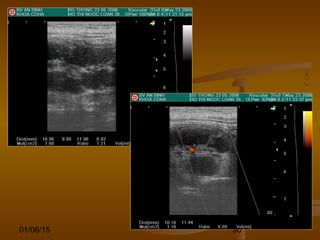

VIÊM RUỘT THỪA CẤP